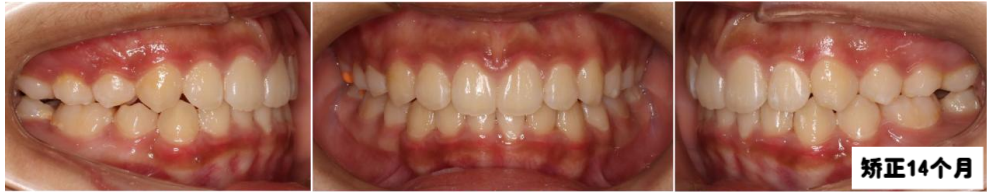

牙齿矫正14个月后,上下颌中线对正,上下牙齿排列整齐,牙弓卵圆形,上下牙弓匹配,前牙达到正常覆合覆盖,牙齿尖窝关系良好。

从牙片资料看上下前牙内收直立,颌平面整平,上颌内收,前牙达到正常覆合覆盖,颏部前伸良好。

青少年时期骨骼有一定的生长发育潜力,适应能力强,牙齿矫正时长相对成人也会较短。